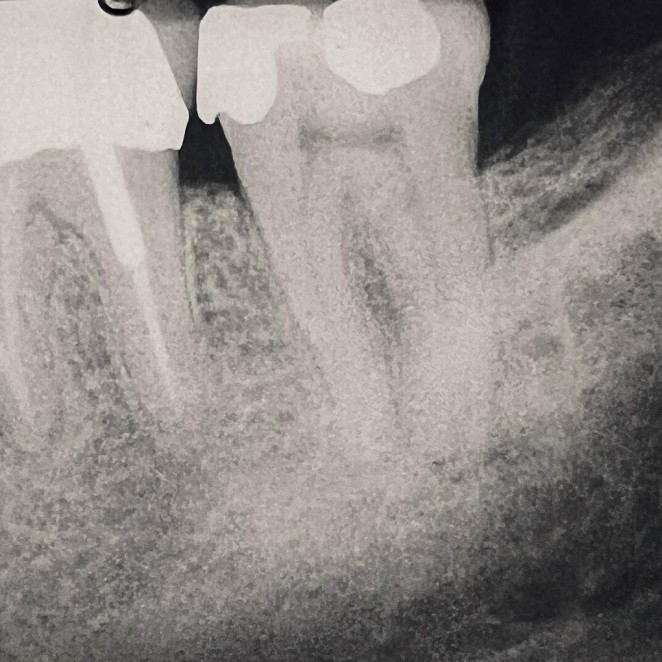

Sometimes, a tooth that has already undergone root canal therapy may not heal as expected or may develop new problems months or even years later. In these cases, endodontic retreatment offers a second chance to save the tooth. During this procedure, the existing filling materials are carefully removed from the canals, the inside of the tooth is cleaned again, and any hidden or untreated areas are addressed before the canals are sealed once more. This process allows your dentist to correct any issues and give the tooth the best possible chance for long-term success.

Thanks to modern tools and techniques, retreatment is a precise and effective procedure that can often be completed comfortably under local anesthesia. Many patients are surprised to learn that retreatment is no more uncomfortable than the original root canal. By choosing retreatment instead of extraction, you preserve your natural tooth, maintain your smile's appearance, and avoid the more complex and costly process of replacing a missing tooth.